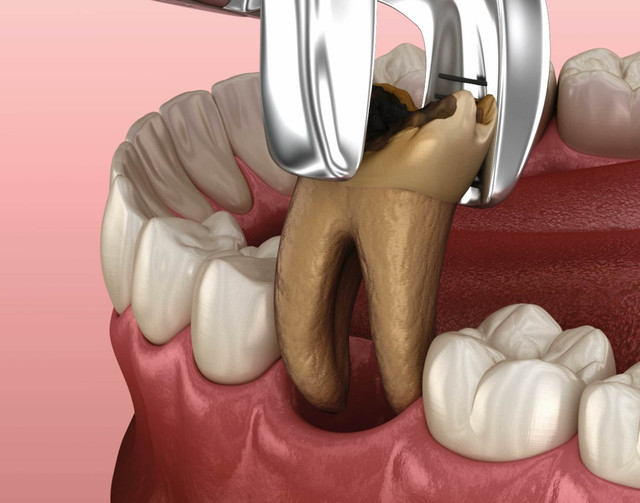

QUY TRÌNH CẮT CHÓP Răng

- 3. Gây tê, tiếp cận và cắt chóp chân răng: Trước khi bắt đầu quy trình, vùng cần điều trị sẽ được gây tê để đảm bảo bạn không cảm thấy đau hoặc khó chịu trong suốt quá trình điều trị. Bác sĩ sẽ tạo đường vào vị trí chóp răng bị nhiễm trùng, loại bỏ khoảng 2mm phần chóp răng, đồng thời làm sạch mô viêm xung quanh.

- 4. Trám ngược chóp răng và khâu đóng vết mổ: Sau khi vùng viêm đã được làm sạch, phần cuối của ống tủy sẽ được trám bít ngược lại bằng vật liệu chuyên dụng để ngăn chặn sự tái nhiễm trùng. Vết mổ sẽ được khâu đóng và lành lại trong vài tuần sau đó.